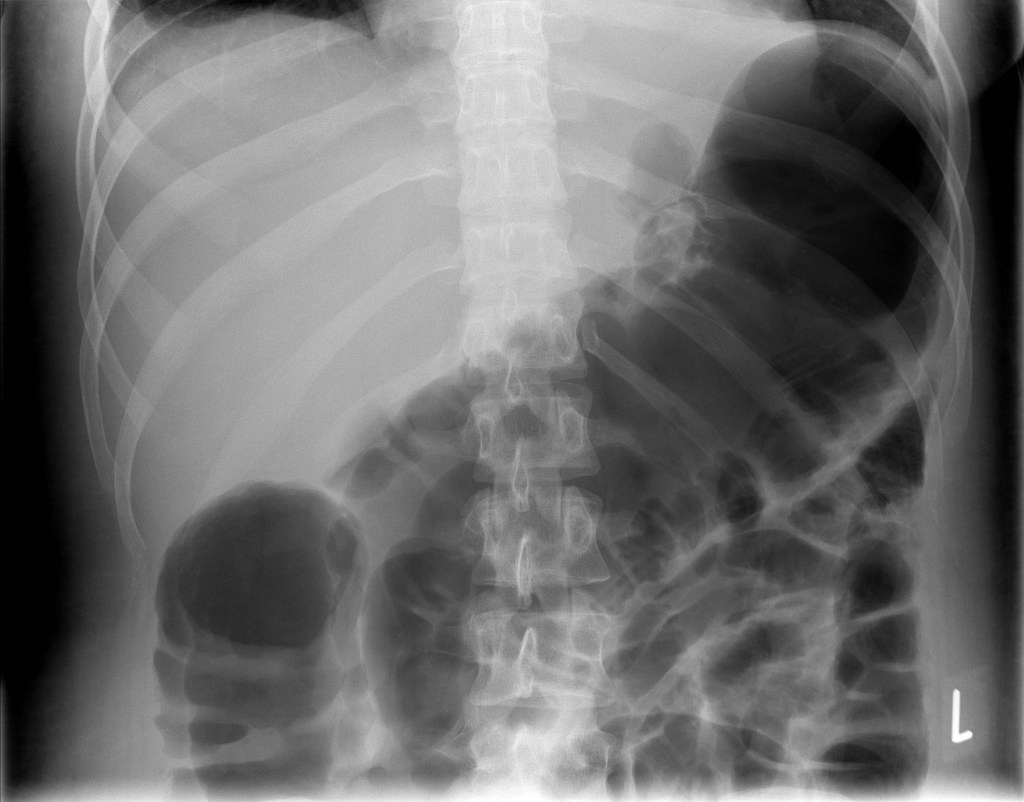

2. 독성 거대결장이 나타날 수 있습니다. 독성 거대결장은 우측 또는 횡행 결장의 지름이 6cm 부푼 경우로 정의합니다.

3. 독성 거대결장은 궤양성 대장염의 약 5%에서 발생하며, 전해질 이상으로 유발될 수 있습니다. 약 50%에서 내과적인 치료로 회복되고 이에 반응하지 않는 경우 응급수술을 해야됩니다.

4. 천공(장에 구멍)이 발생할 수 있습니다. 천공이 생기고 장안의 세균이 복강으로 나와 복막염이 발생할 수 있습니다. 하지만 궤양성 대장염 치료로 스테로이드를 사용하여 염증을 억제하기 때문에 복막염을 확인하기 어려울 수 있다고 합니다.

5. 독성 거대결장과 천공이 동시에 발생한 경우 사망률이 15%에 이릅니다.